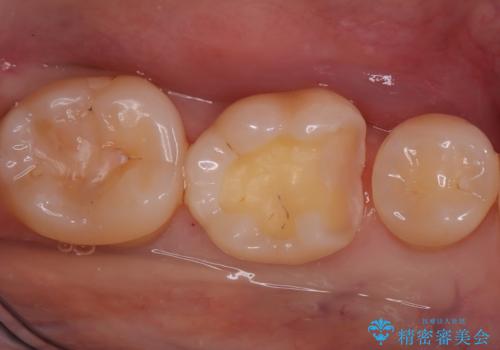

- 「銀歯を白くしたい」を主訴に来院された患者さんです。 左下6番に銀歯を被せてあり、一部分が欠けている状態でした。

銀歯と虫歯を除去しハイブリッドインレーで治療を行いました。